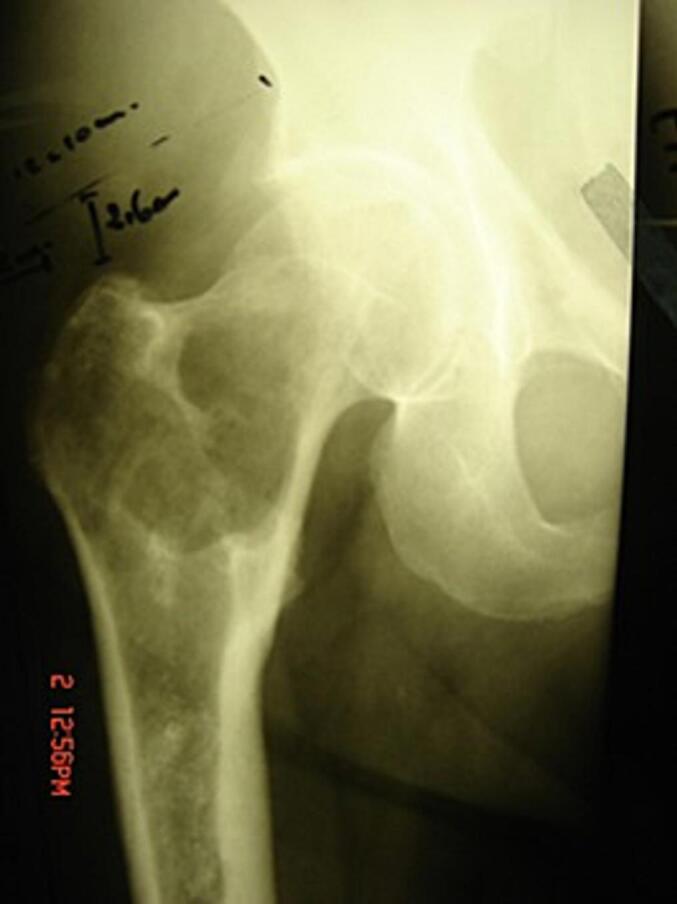

Case presentation: A 60-year-male presenting with features of proximal femur chondrosarcoma as seen on radiography and suspected on biopsy. He underwent wide-margin surgical resection and salvage uncemented total hip arthroplasty using modular endoprosthesis with autograft, allograft and bone substitute wrapped within a polypropylene mesh (morselized). Xray at 2 months postoperatively showed a faster and early evidence of new bone formation between the HA-coated femoral stem and bone graft within the mesh.